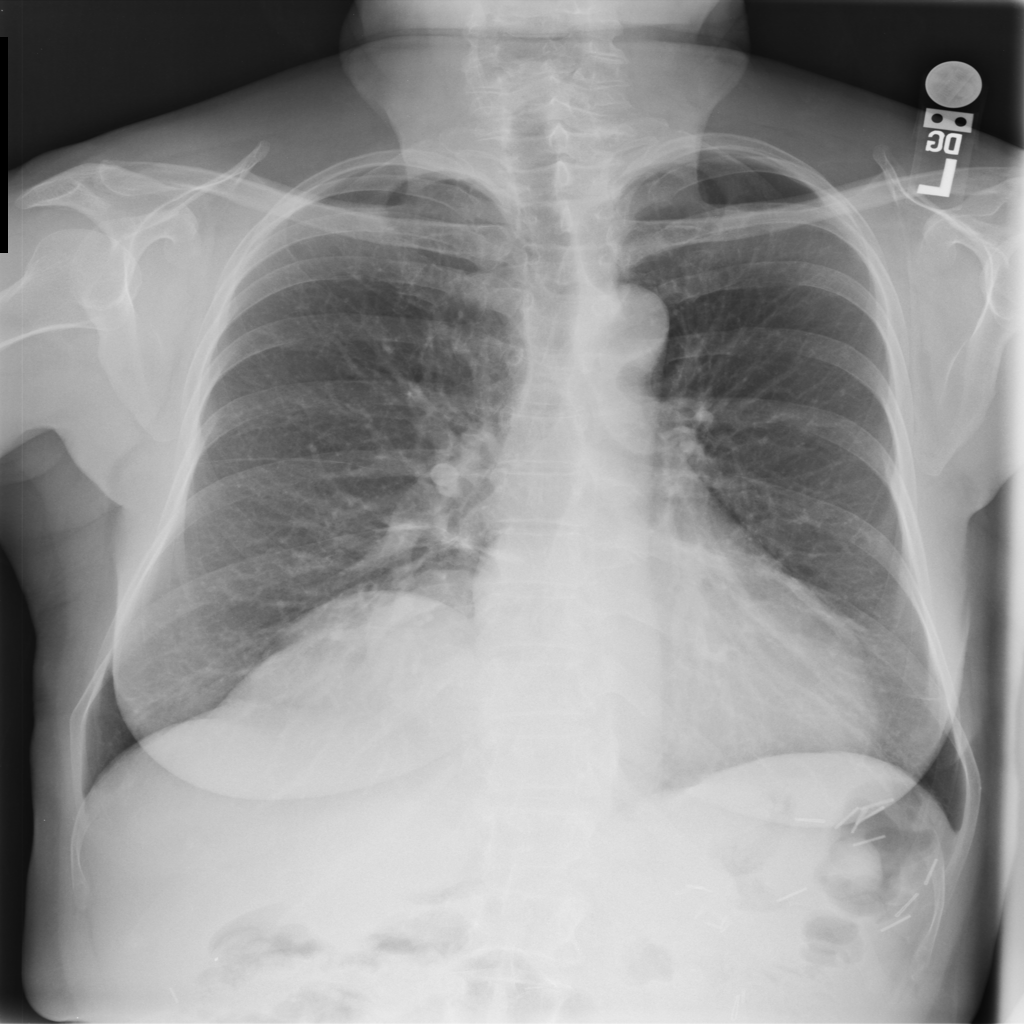

PAT-C048 · IMG-001Hernia

PAT-C048 · IMG-001

PA